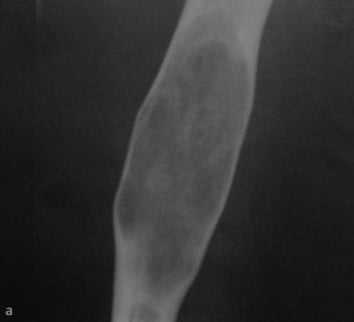

a-d Фиброзная дисплазия. Женщина 48 лет с фиброзной дисплазией, поражающей дистальный отдел плечевой кости: a) На рентгенограмме диафиза плечевой кости определяется кистозное географическое поражение с пузырным расширением. Типичное изображение в виде «битого стекла»;

b) Аксиальная Т1- взвешенная последовательность. Гипоинтенсивное поражение с истончением кортикального слоя.